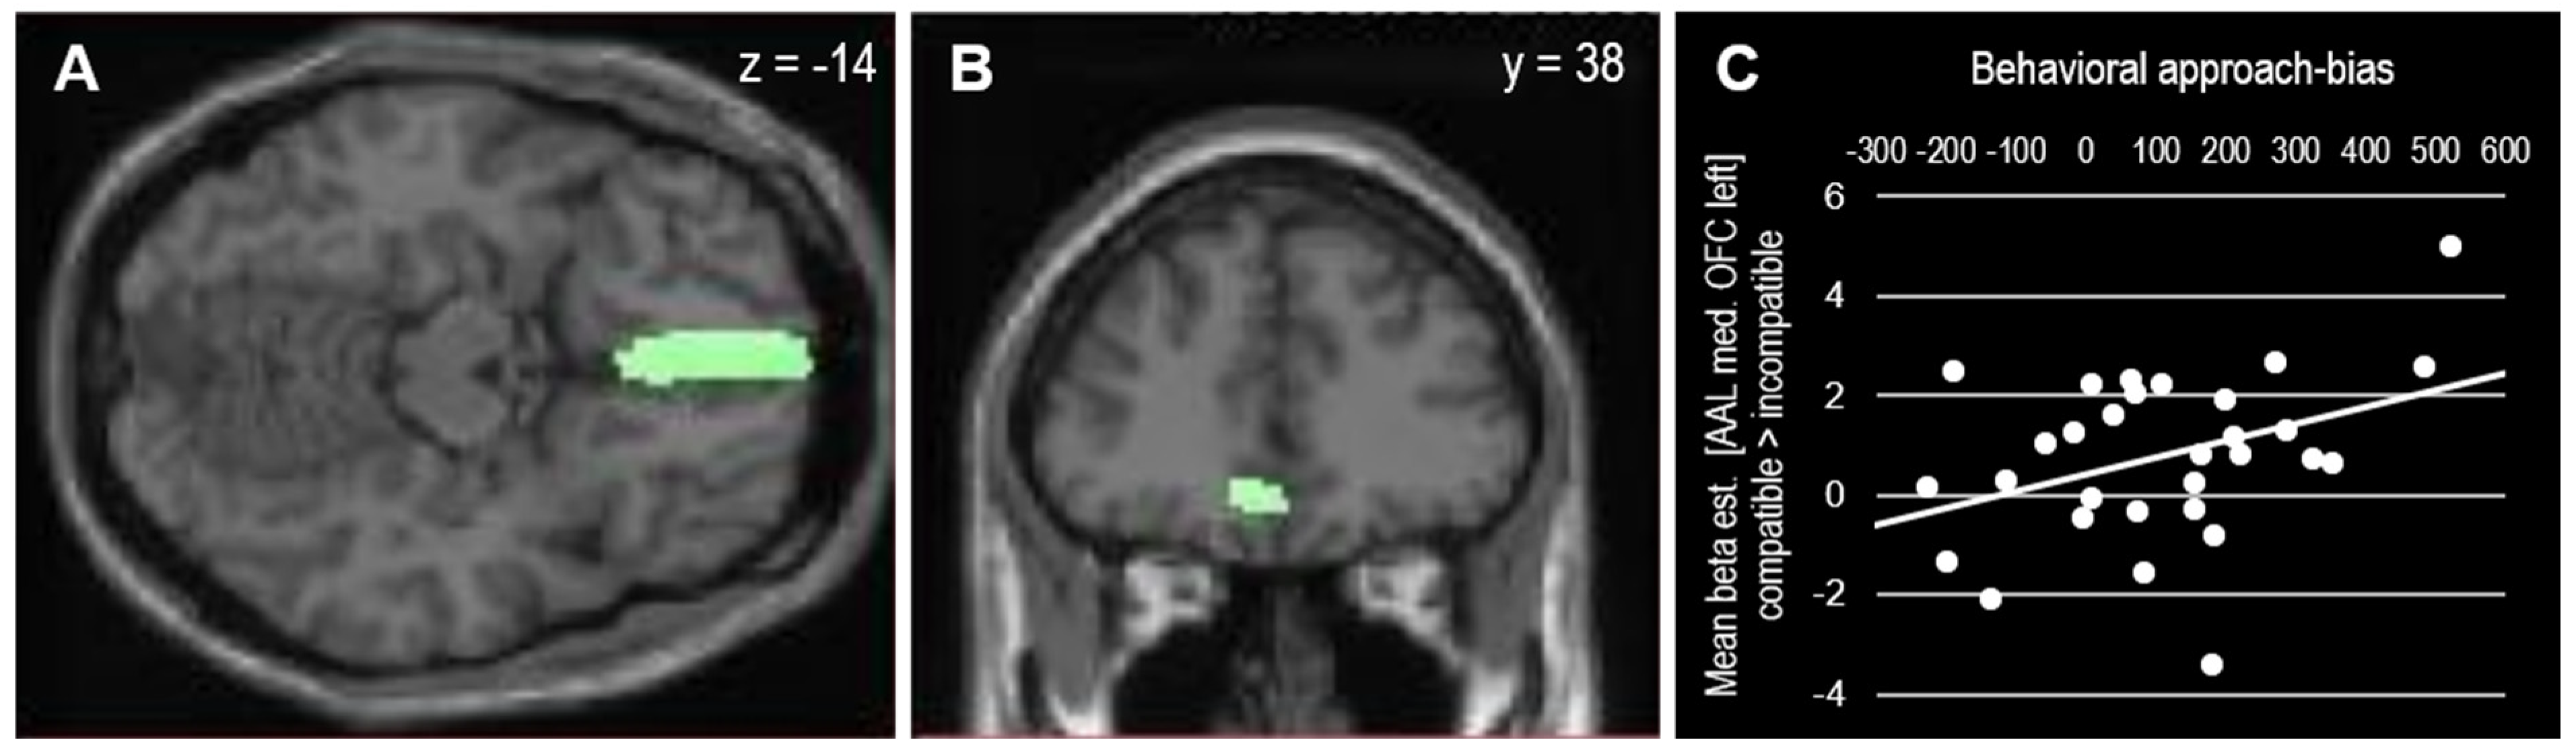

This approach bias-related OFC activation correlated positively with the behavioral approach bias scores (r(28) = 0.38, p = 0.038), as depicted in Figure 4. To take the block-order effect into account, the correlation was computed for both orders separately. In line with the pattern observed in the behavioral analysis, the correlation between individual approach bias scores and medial OFC activation was mainly driven by participants who performed the compatible block at first (r(13) = 0.72, p = 0.003) but not by participants who performed the compatible block as the second block (r(13) = −0.07, p = 0.807).

Figure 4.

(A,B) Mask (AAL medial OFC left) used for SVC (psvc = 0.023 FWE-corrected at cluster level). (C) Extracted beta-estimates from OFC mask and their association with behavioral approach bias scores (r(28) = 0.381, p = 0.038).